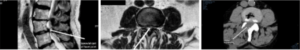

A 77 year-old man presented with bilateral leg pain on walking and standing. His MRI scan showed a tight stenosis at L3/4 due to degenerative changes, with an associated synovial cyst of the right L3/4 facet joint. He proceeded to surgery, and a keyhole L3/4 decompression was performed, approached from the right hand side of L3/4. See scans below.

Figures 1 & 2 - Pre-op MRI